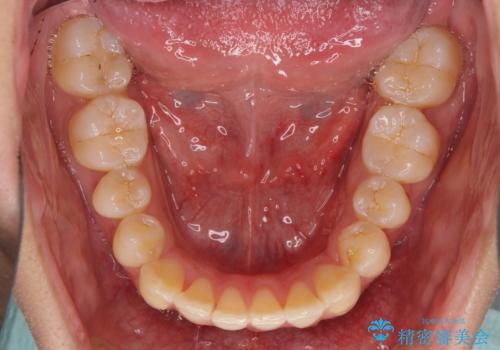

全体的に軽微な叢生が認められ、口元もやや前方に突出していたため、インビザラインでのIPR(歯と歯の間を削る)と歯列全体の後方移動によって歯並びを整えることとしました。

上下ともに歯列の幅が狭かったため、側方に拡大することで前歯のデコボコや突出感を解消するためのスペースを獲得することができました。